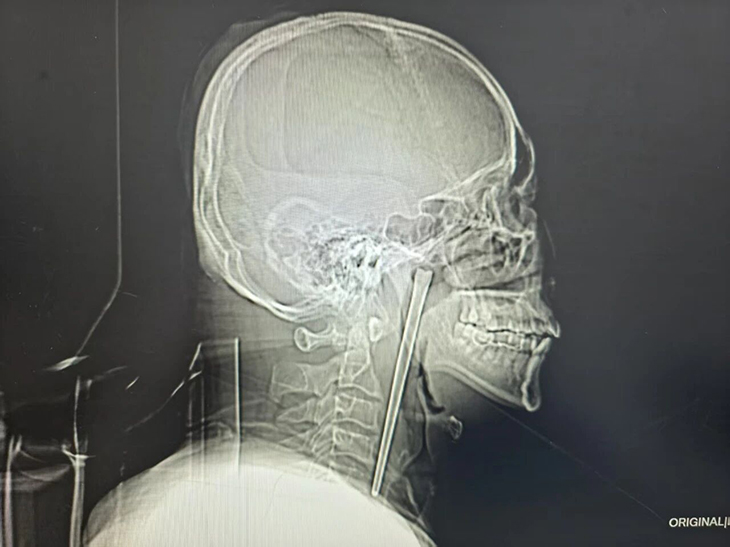

O caso só veio a ser descoberto quando o homem, de 46 anos, apareceu no hospital com dores intensas e aquela sensação estranha de “qualquer coisa aqui dentro não devia estar aqui dentro”. Uma radiografia resolveu o mistério em segundos: um objeto metálico comprido, bem instalado na sua garganta como se tivesse assinado contrato de arrendamento de longa duração.

Quando os médicos perguntaram o inevitável “como é que isto aconteceu?”, Wang respondeu com a tranquilidade de quem fala do tempo: tinha engolido um pau de metal enquanto comia, há oito anos. Detalhes mais precisos não foram fornecidos, mas há um pequeno contexto relevante mencionado no hospital — o homem tinha histórico de consumo de álcool, o que ajuda a explicar como alguém consegue confundir talheres com “experiências culinárias de risco extremo”.

Quando finalmente foi operado, os médicos conseguiram remover o objeto por via minimamente invasiva, sem necessidade de cirurgia mais agressiva. O mais impressionante? O tal “intruso” saiu praticamente intacto, como se tivesse passado oito anos apenas à espera do momento certo para ser retirado.